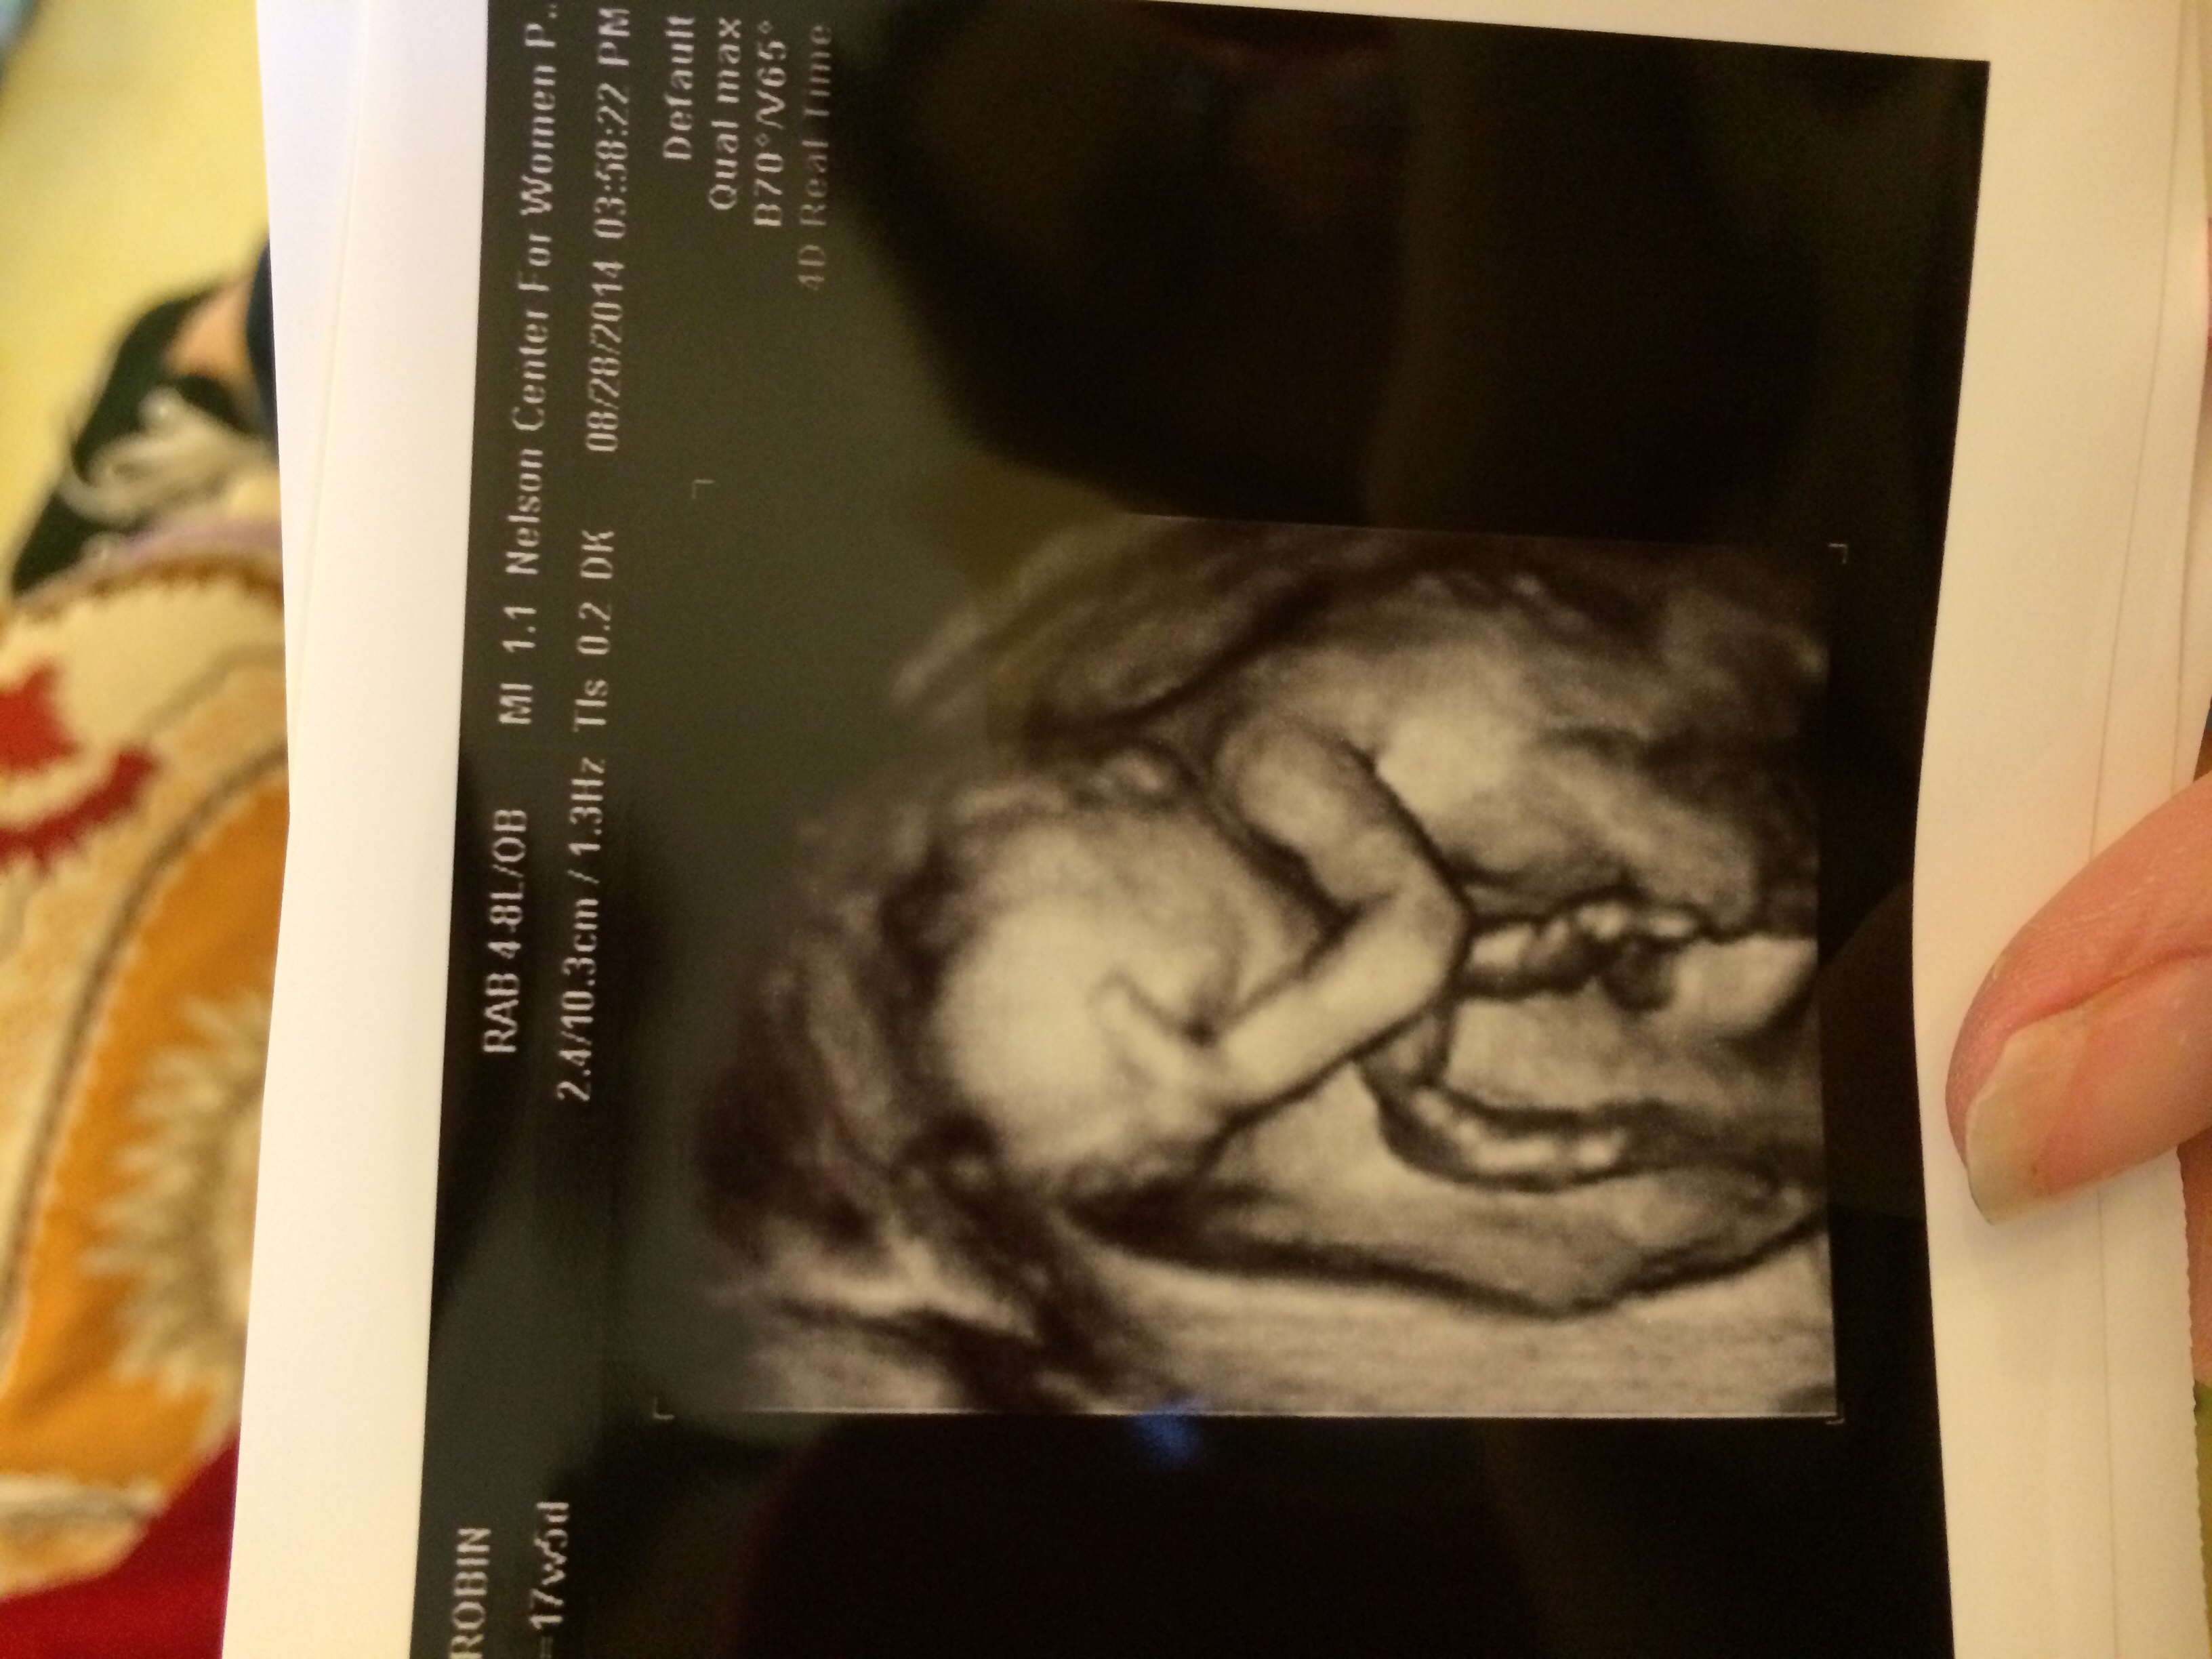

My baby has an attitude already

His hand is on his head and he was mad!!

haha Face Palm!

Lol. So cute! Like Do'h Mama!

So cute! Maybe he's just being shy and doesn't like being the center of attention!

ha! my lil man had the same thing, except his hand was facing the other way...so dramatic...like, "Woe is me, my life is so rough" Too cute.